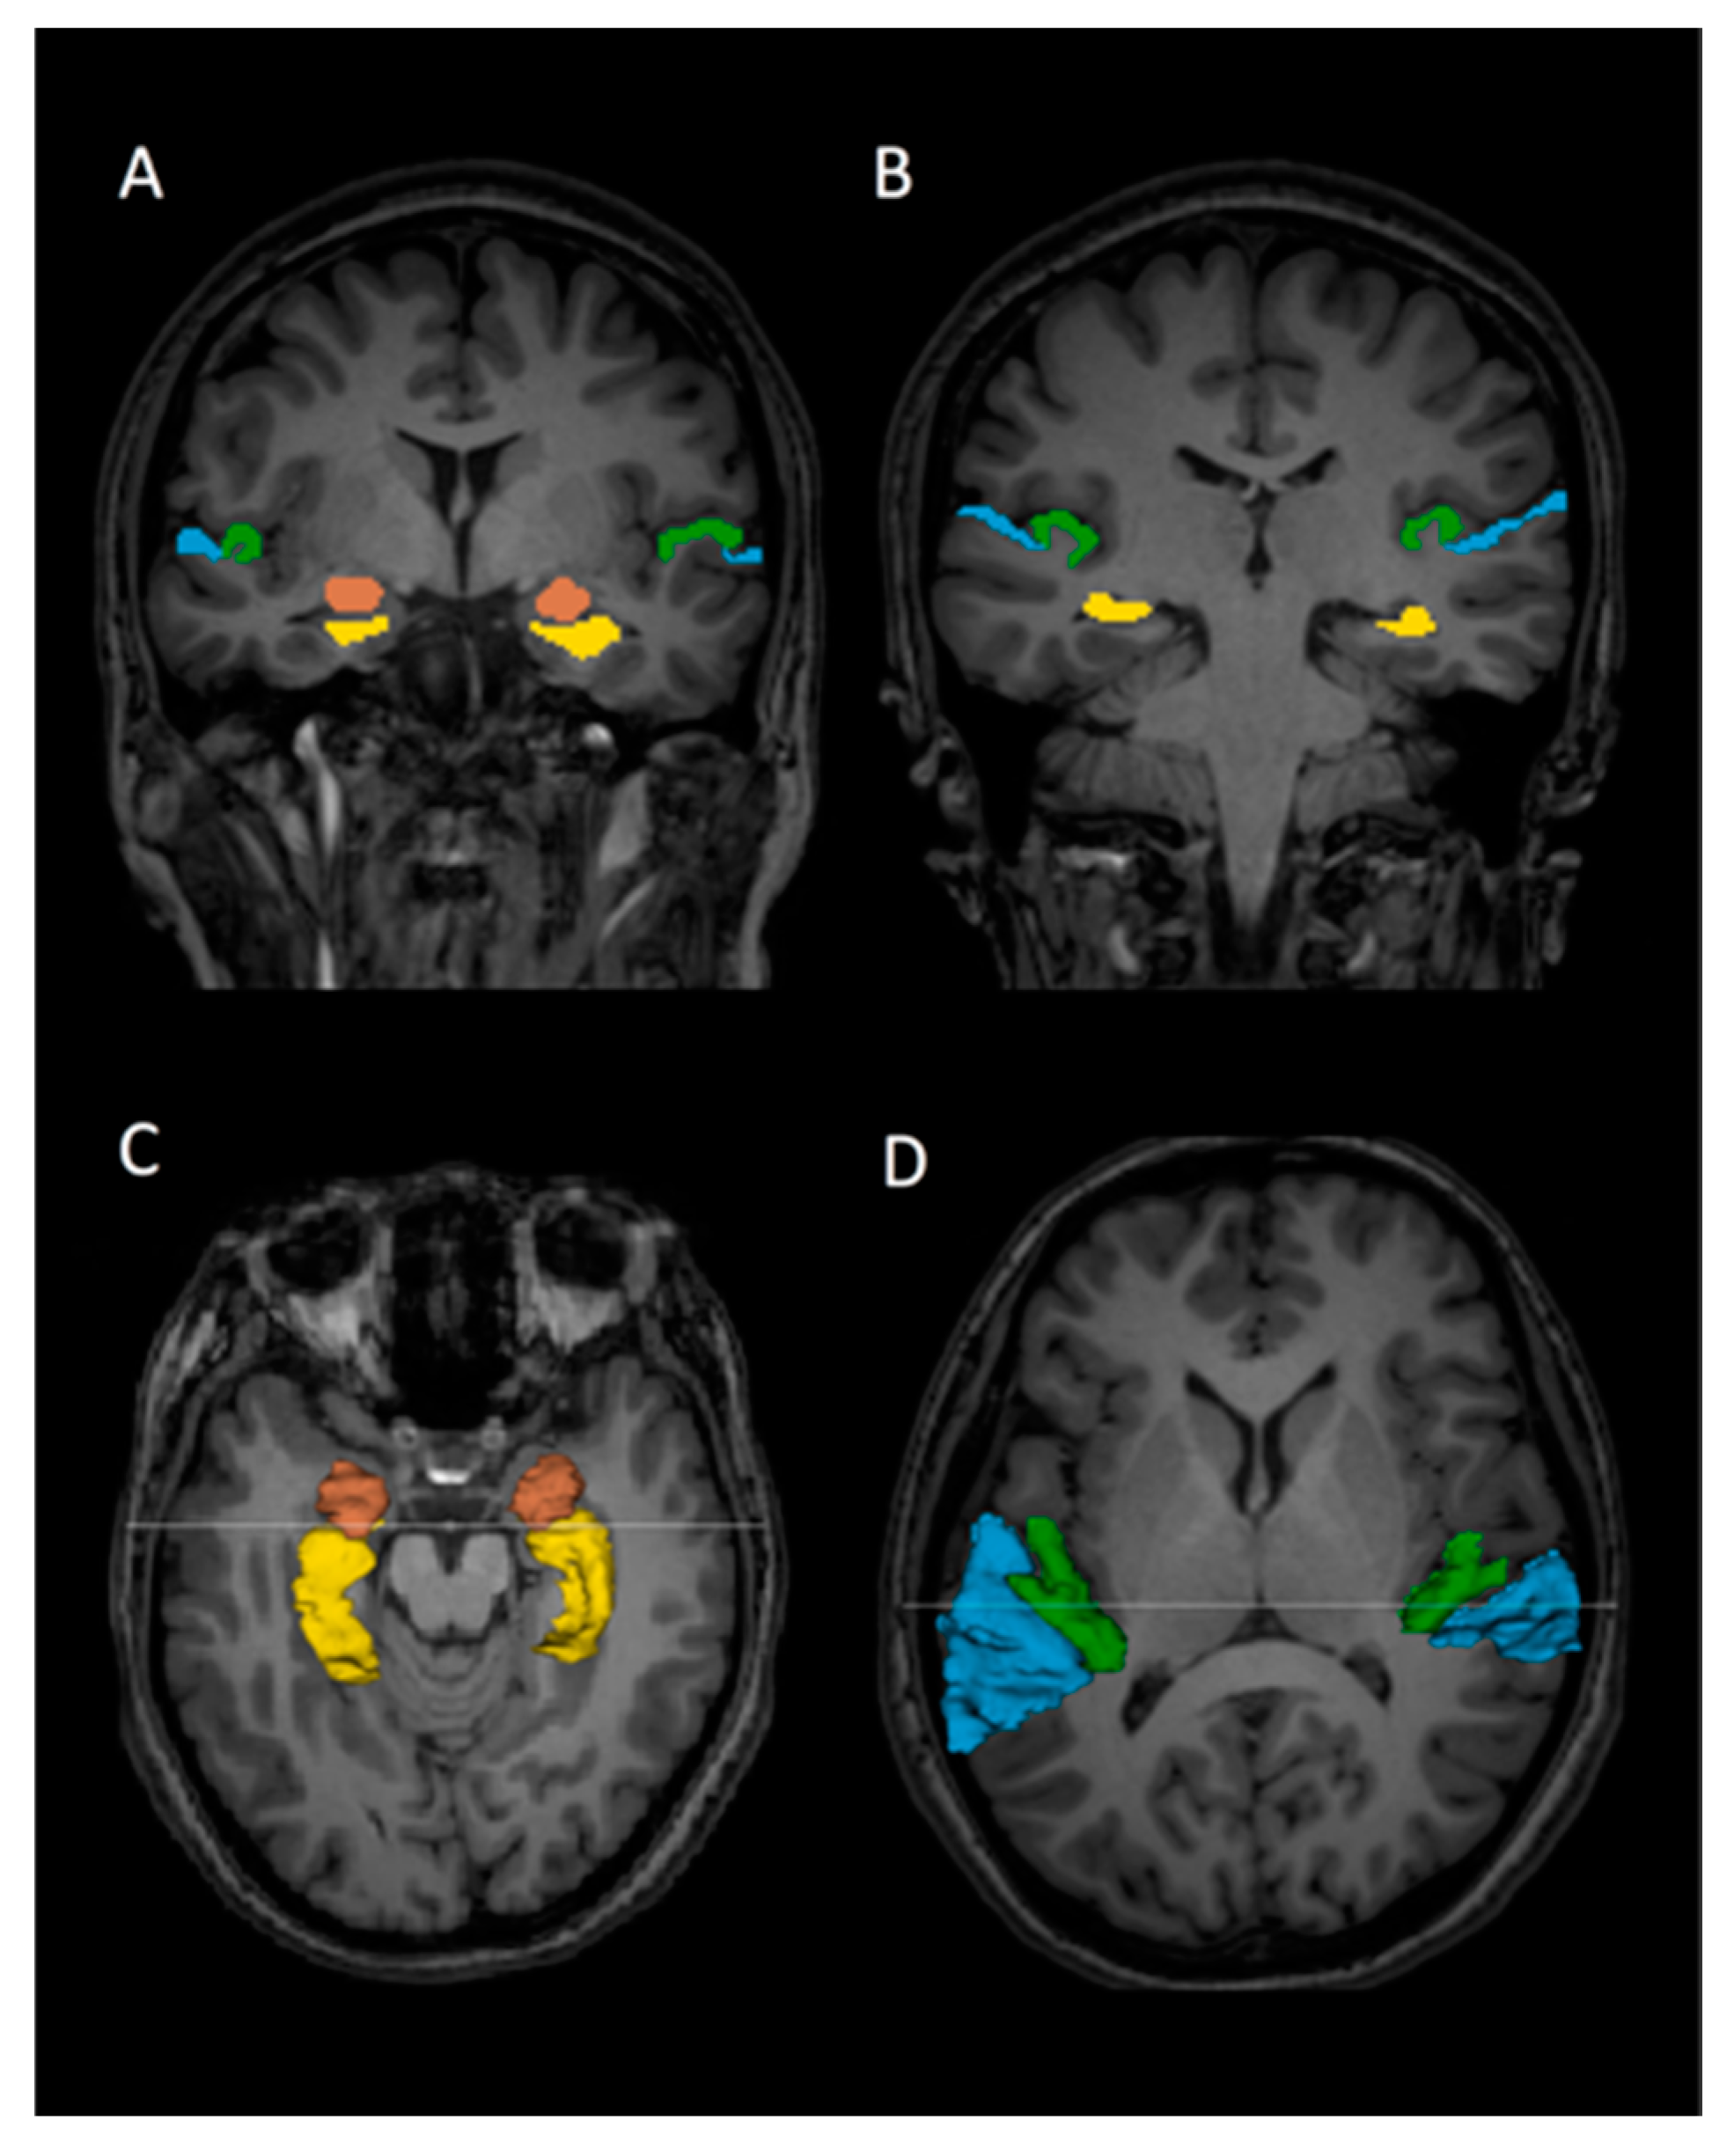

2.3. Regions of Interest and Volume Measurement